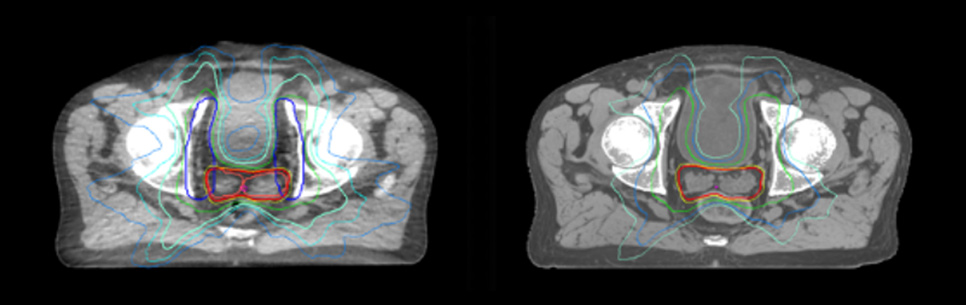

Dosimetric equivalence validation was performed on 43 patient cases by comparing MRCAT-based dose plans overlaid on CBCT image dataset and on the corresponding MRCAT image dataset. Mr. Bolard and Dr. Champion found good agreement between MRCAT-based and CT-based dose calculations, with a mean dose ratio of 1.007 (0.991-1.014). The 3D gamma score was greater than 95% (95.2-99.0%) for all plans checked. A poster on this work was accepted for presentation at ESTRO 2020.

Dose plans overlaid on CBCT image dataset (left) and on MRCAT image dataset (right).